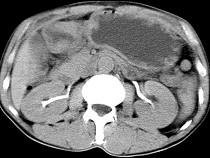

问题 男,56岁,无规律上腹痛,左锁骨上淋巴结肿大,消瘦、乏力,影像检查如图,最可能的诊断是()

选项 A.腹膜结核 B.胃溃疡穿孔 C.胃癌并盆腔种植 D.胃及腹腔淋巴瘤 E.肠系膜淋巴管瘤

答案 C